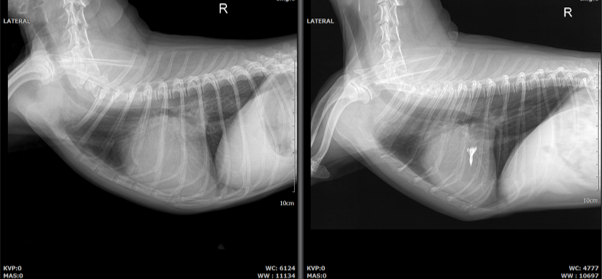

3. 호흡기계 중재치료

내과적 치료로 관리가 가능한 기관 허탈에서 심화된 기관 협착의 정도가 심해지면 기침, 과호홉, 좌위호흡 등 호흡곤란과 청색증을 보입니다. 이러한 환자들에게 호흡을 위한 공간을 만들어주기 위해 기관에 스텐트를 삽입하여 기관을 확장하는 시술을 합니다. 본원에서는 대부분의 환자에게 적용 가능한 강아지 기관 전용 스텐트를 사용하며 숙련된 전문의가 시술을 진행합니다.